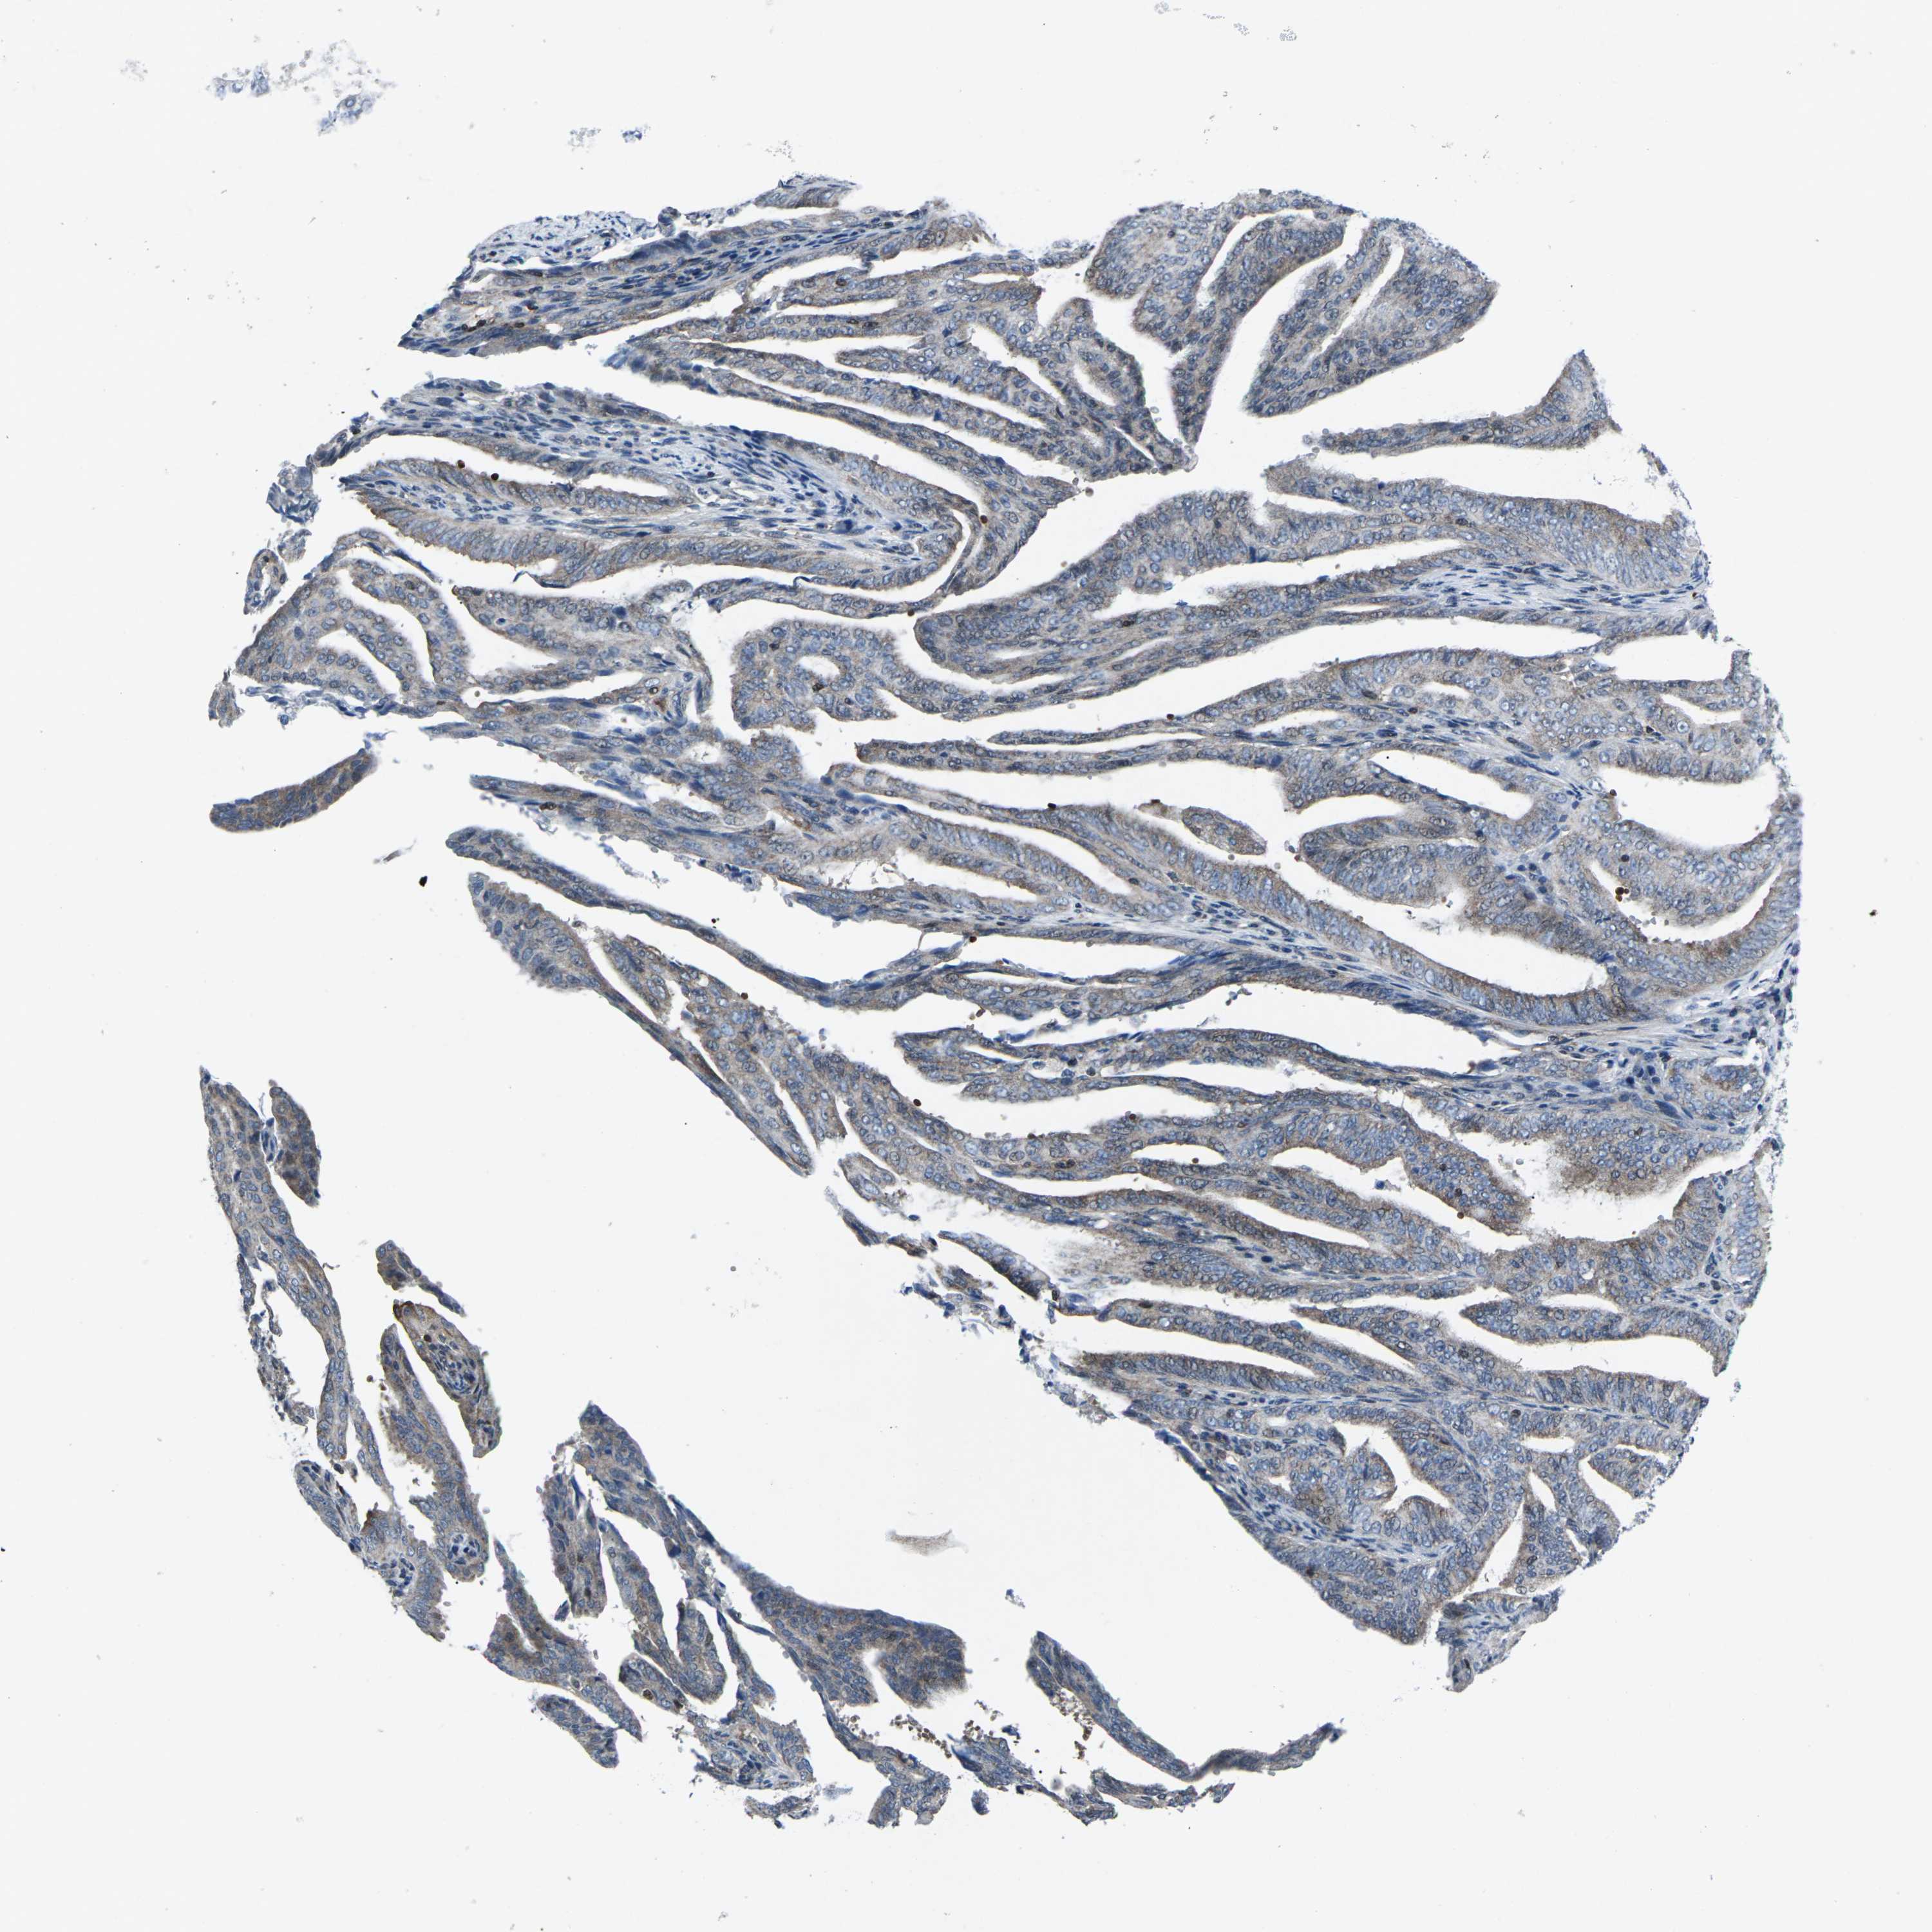

ENDOMETRIAL CANCER - Protein expressioni

A mouse-over function shows sample information and annotation data. Click on an image to view it in a full screen mode. Samples can be filtered based on level of antibody staining by selecting one or several of the following categories: high, medium, low and not detected. The assay and annotation is described here.

Note that samples used for immunohistochemistry by the Human Protein Atlas do not correspond to samples in the TCGA dataset.

Antibody stainingi

Antibody staining in the annotated cell types in the current human tissue is reported as not detected, low, medium, or high, based on conventional immunohistochemistry profiling in selected tissues. This score is based on the combination of the staining intensity and fraction of stained cells.

Each image is clickable and will lead to virtual microscopy that enables deeper exploration of all samples and also displays staining intensity scores, fraction scores and subcellular localization as well as patient and tissue information for each sample.

Antibody HPA001860

Antibody CAB013108

Staining

High

Medium

Low

Not detected

Intensity

Strong

Moderate

Weak

Negative

Quantity

>75%

75%-25%

<25%

None

Location

Nuclear

Cytoplasmic/membranous

Cytoplasmic/membranous,nuclear

Adenocarcinoma, NOS

Neoplasm, malignant, NOS